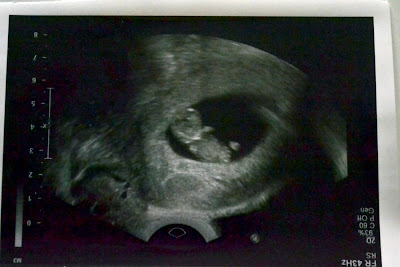

Oh, and I've been feeling the baby for a couple of days. I always feel them so early! :) :) LOVE feeling my baby kick ..... LOVE IT.